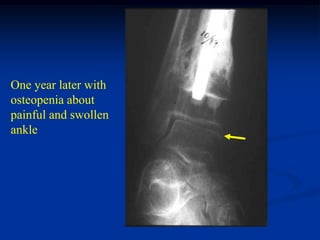

One year later with

osteopenia about

painful and swollen

ankle